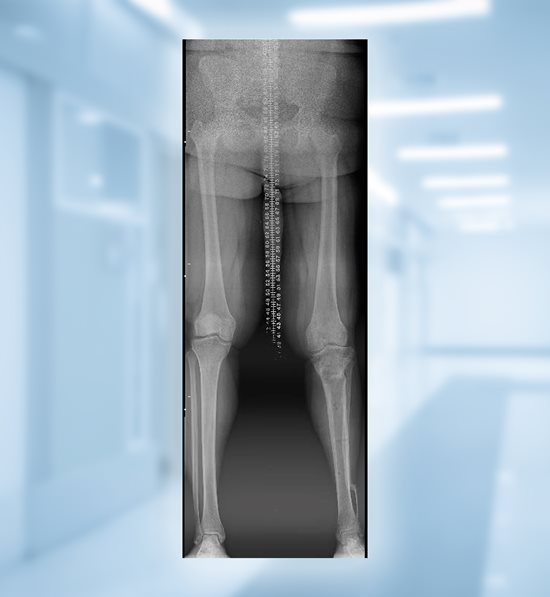

Bianca gets her inspiration through her own personal story. She suffered from pain and a severe bowleg deformity for many years as a result of Blount’s disease, a growth disorder that affects the bones in children and young adults. Although Bianca underwent several surgeries as a child for the condition, she had gradual worsening of her knee, began experiencing pain, and started to develop stress fractures at the age of 18.

Dr. Scott Schoenleber, pediatric orthopedic surgeon at Nicklaus Children’s Hospital, recommended osteotomies and gradual realignment with an external fixator to help shift her bones into the correct position.

"Bianca had a complex condition which placed a lot of abnormal stress on the tibia and knee. This was causing her a lot of pain and interfering with her ability to walk and remain active, so we recommended surgery. The first of two procedures involved an osteotomy of the tibia and fibula with placement of an external fixator that would allow the bones to gradually be brought into proper alignment. The second surgery, which took place three or four months later, was done to remove the fixator,” said Dr. Schoenleber.

By positioning the knee in line with the body’s natural center of gravity, this surgery is helping Bianca with her overall balance, maintaining equal forces across the knee, and slowing the progression of arthritis. Dr. Schoenleber says one of the most important parts of this procedure is ensuring the patient recovers well through frequent follow up visits.